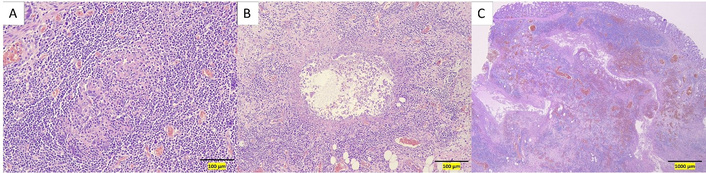

An initial loading dose of IV infliximab 10 mg/kg was administered without any immediate issues. Later that evening, while ambulating to the restroom, the patient experienced severe left upper quadrant pain radiating to the left arm, accompanied by shortness of breath. A STAT abdominal radiograph showed significant intraperitoneal free air and marked colonic dilation with large air-fluid levels (Figure 3). She was immediately started on broad-spectrum antibiotics (IV piperacillin-tazobactam 3.375 g every 6 hours) and taken emergently to the operating room. Exploratory laparotomy revealed gross perforations at the splenic flexure, transverse colon, and ascending colon near the cecum, with pronounced inflammation in the left colon. An extended right hemicolectomy with end ileostomy was performed. Pathologic evaluation of the resected specimen showed severe acute colitis with ulceration, submucosal and subserosal abscesses, transmural inflammation, and non-caseating granuloma formation characterized by the presence of epithelioid cells, multinucleated giant cells, and lymphocytes, without necrosis (Figure 4).

Hematoxylin and eosin-stained sections of the resected colectomy specimen. (A) High-power view showing a non-caseating granuloma. (B) High-power view showing a submucosal abscess. (C) Low-power view demonstrating acute, severe transmural inflammation.